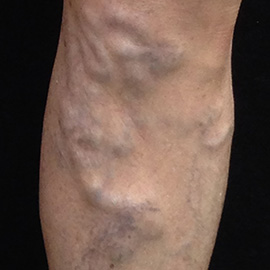

靜脈曲張

站立時,可以在小腿內側看到像蚯蚓一般,摸起來軟軟的,扭曲變形鼓出的血管,直徑大於0.3公分,這類型的靜脈曲張會影響腿部的血液循環、如果放任惡化沒有治療、皮膚會逐漸出現濕疹及潰瘍。